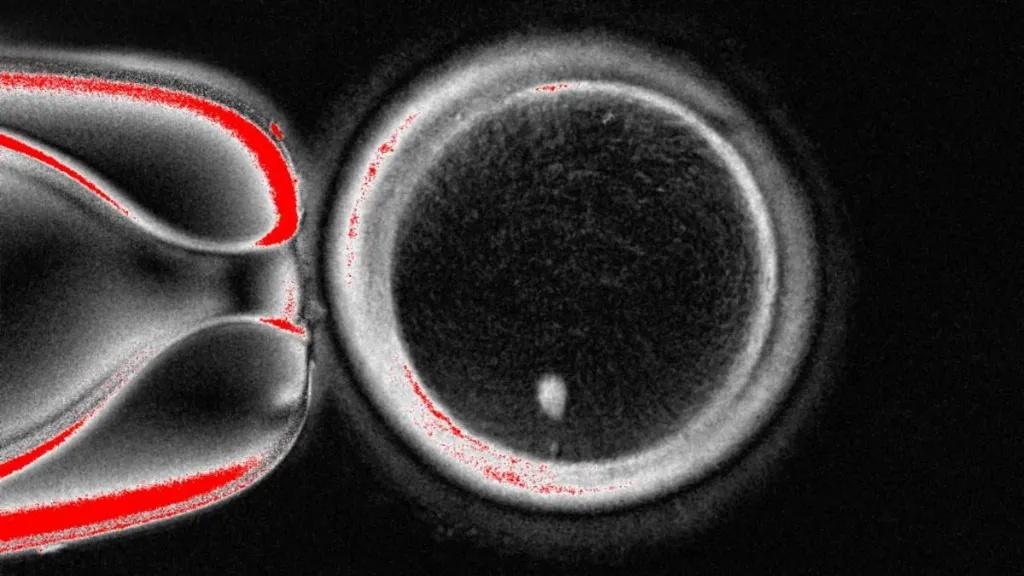

Above: An image of a cell from OHSU. Image credit: OHSU via X